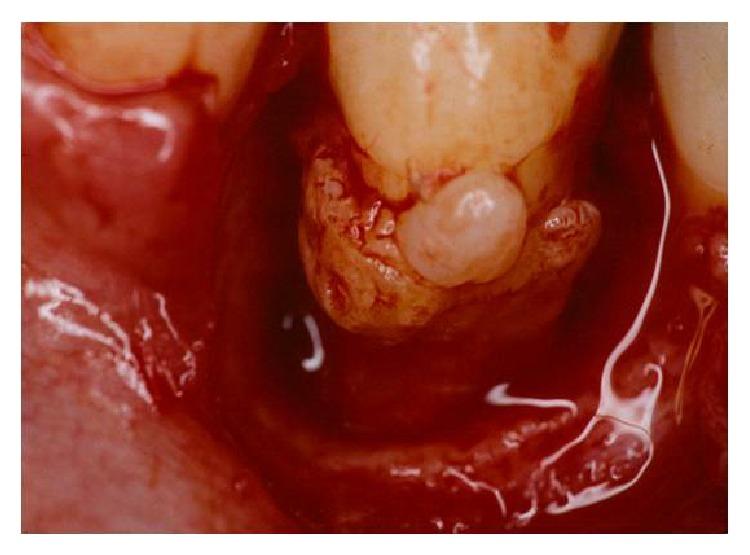

Dental anatomy is quite complex and diverse factors must be taken into account in its analysis. Teeth with anatomical variations present an increase in the rate of severity periodontal tissue destruction and therefore a higher risk of developing periodontal disease. In this context, this paper reviews the literature regarding enamel pearls and their implications in the development of severe localized periodontal disease as well as in the prognosis of periodontal therapy. Radiographic examination of a patient complaining of pain in the right side of the mandible revealed the presence of a radiopaque structure around the cervical region of lower right first premolar. Periodontal examination revealed extensive bone loss since probing depths ranged from 7.0 mm to 9.0 mm and additionally intense bleeding and suppuration. Surgical exploration detected the presence of an enamel pearl, which was removed. Assessment of the remaining supporting tissues led to the extraction of tooth 44. Local factors such as enamel pearls can lead to inadequate removal of the subgingival biofilm, thus favoring the establishment and progression of periodontal diseases.

牙齿解剖结构相当复杂,在分析时必须考虑多种不同因素。存在解剖变异的牙齿会使牙周组织破坏的严重程度增加,因此患牙周病的风险更高。在此背景下,本文回顾了有关釉珠及其在严重局限性牙周病发展以及牙周治疗预后方面影响的文献。对一名主诉下颌右侧疼痛的患者进行的影像学检查显示,右下第一前磨牙颈部区域周围存在一个不透射线的结构。牙周检查发现广泛的骨质流失,因为探诊深度在7.0毫米至9.0毫米之间,此外还有严重出血和化脓。手术探查发现存在一颗釉珠,并将其取出。对剩余支持组织的评估导致拔除了44号牙。诸如釉珠等局部因素会导致龈下生物膜清除不充分,从而有利于牙周病的形成和进展。